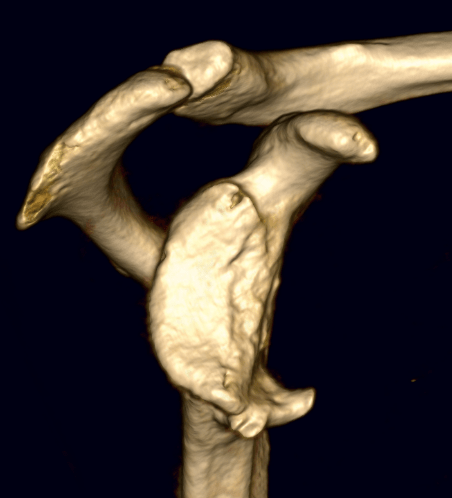

Dr Tim Dwyer is an orthopedic surgeon specializing in sports medicine and arthroscopy, performing surgery of the hip, knee and shoulder. Based at Women’s College and Mt Sinai Hospital, Dr Dwyer performs high volume ACL reconstruction, hip arthroscopy, rotator cuff repair, and operations for shoulder dislocation.